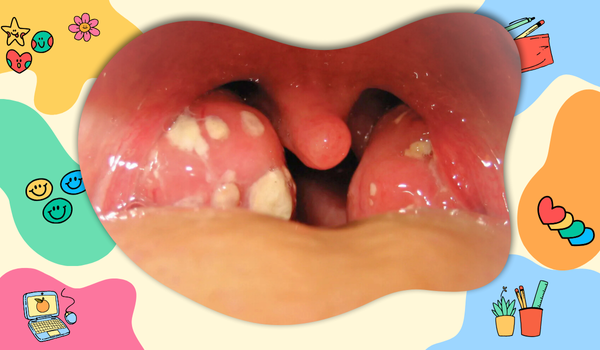

Tonsillitis can affect both children and adults, although it is more common in children. The condition occurs when the tonsils, which are part of the body’s immune system and help fight infections, become infected themselves. Inflammation leads to discomfort and can sometimes cause complications such as ear pain or an abscess (a collection of pus). Tonsillitis can be classified as either acute (short-term) or chronic (long-term). Acute tonsillitis usually resolves with treatment, while chronic tonsillitis may require more extensive interventions like a tonsillectomy (surgical removal of the tonsils).